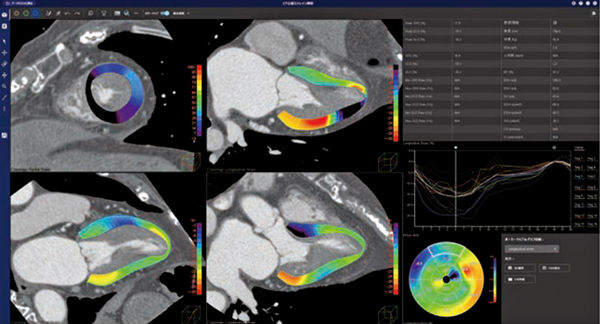

MRIによる心筋ストレイン評価は,心筋運動による壁厚の変化を定量的に評価する方法であり,日本循環器学会の「2020年版 心アミロイドーシス診療ガイドライン」ではクラスⅡaとして推奨されている。REVORASの「MR心筋ストレイン解析」では,MRIのデータを開いた後,短軸像および長軸像(2ch,3ch,4ch)のすべての断面において,左室心筋内壁と外壁の輪郭線が自動で抽出される。手動で輪郭線の修正を行った場合も,各スライスやフェーズにおいて輪郭線が自動で補間されるため,効率的に解析作業を行うことができる。円周方向(circumferential strain),心筋の中心部方向(radial strain),左室長軸方向(longitudinal strain)の3方向での評価に加え,各セグメントのストレイン評価やポーラーマップでの解析結果の表示も可能である(図3)。

図3 MR心筋ストレイン解析